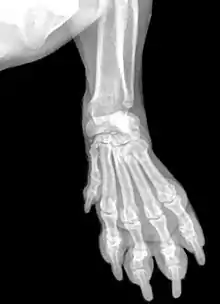

Лапа — ступня либо вся конечность у некоторых млекопитающих. Лапа, в противоположность копыту, является, в основном, мягким окончанием конечности. Передние и задние лапы соответствуют рукам и ногам, соответственно, у высших приматов и людей. Основное предназначение лап — передвижение.

Основной признак лапы — это наличие мягких кожистых образований, называемых подушечками. Центральная из них имеет больший размер и сердцеобразную форму, она прикрепляется к пястью (в случае с передними лапами) или к плюсне (на задних лапах). Остальные подушечки находятся на пальцах, обычно их четыре, но бывают и пять, у медведей, и шесть, у больших панд. Как правило, подушечки лап покрыты плотной безволосой кожей, для сопротивления изнашиваемости из-за ходьбы. Но вот у красной панды подушечки покрыты шерстью, что помогает в холодном климате.